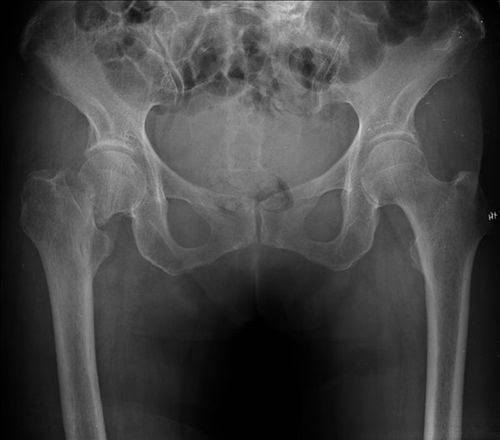

老年人跌倒后诉髋部疼痛,不能站立和走路,应想到股骨颈骨折的可能。

(1)畸形:患肢多有轻度屈髋屈膝及外旋畸形。

(2)疼痛:髋部除有自发疼痛外,移动患肢时疼痛更为明显。在患肢足跟部或大粗隆部叩打时,髋部也感疼痛,在腹股沟韧带中点下方常有压痛。

(3)肿胀:股骨颈骨折多系囊内骨折,骨折后出血不多,又有关节外丰厚肌群的包围,因此,外观上局部不易看到肿胀。

(4)功能障碍:移位骨折病人在伤后不能坐起或站立,但也有一些无移位的线状骨折或嵌插骨折病例,在伤后仍能走路或骑自行车。对这些病人要特别注意,不要因遗漏诊断使无移位稳定骨折变成移位的不稳定骨折。在移位骨折,远端受肌群牵引而向上移位,因而患肢变短。

(5)患侧大粗隆升高表现在:

①大粗隆在髂-坐骨结节联线之上;

②大粗隆与髂前上棘间的水平距离缩短,短于健侧。